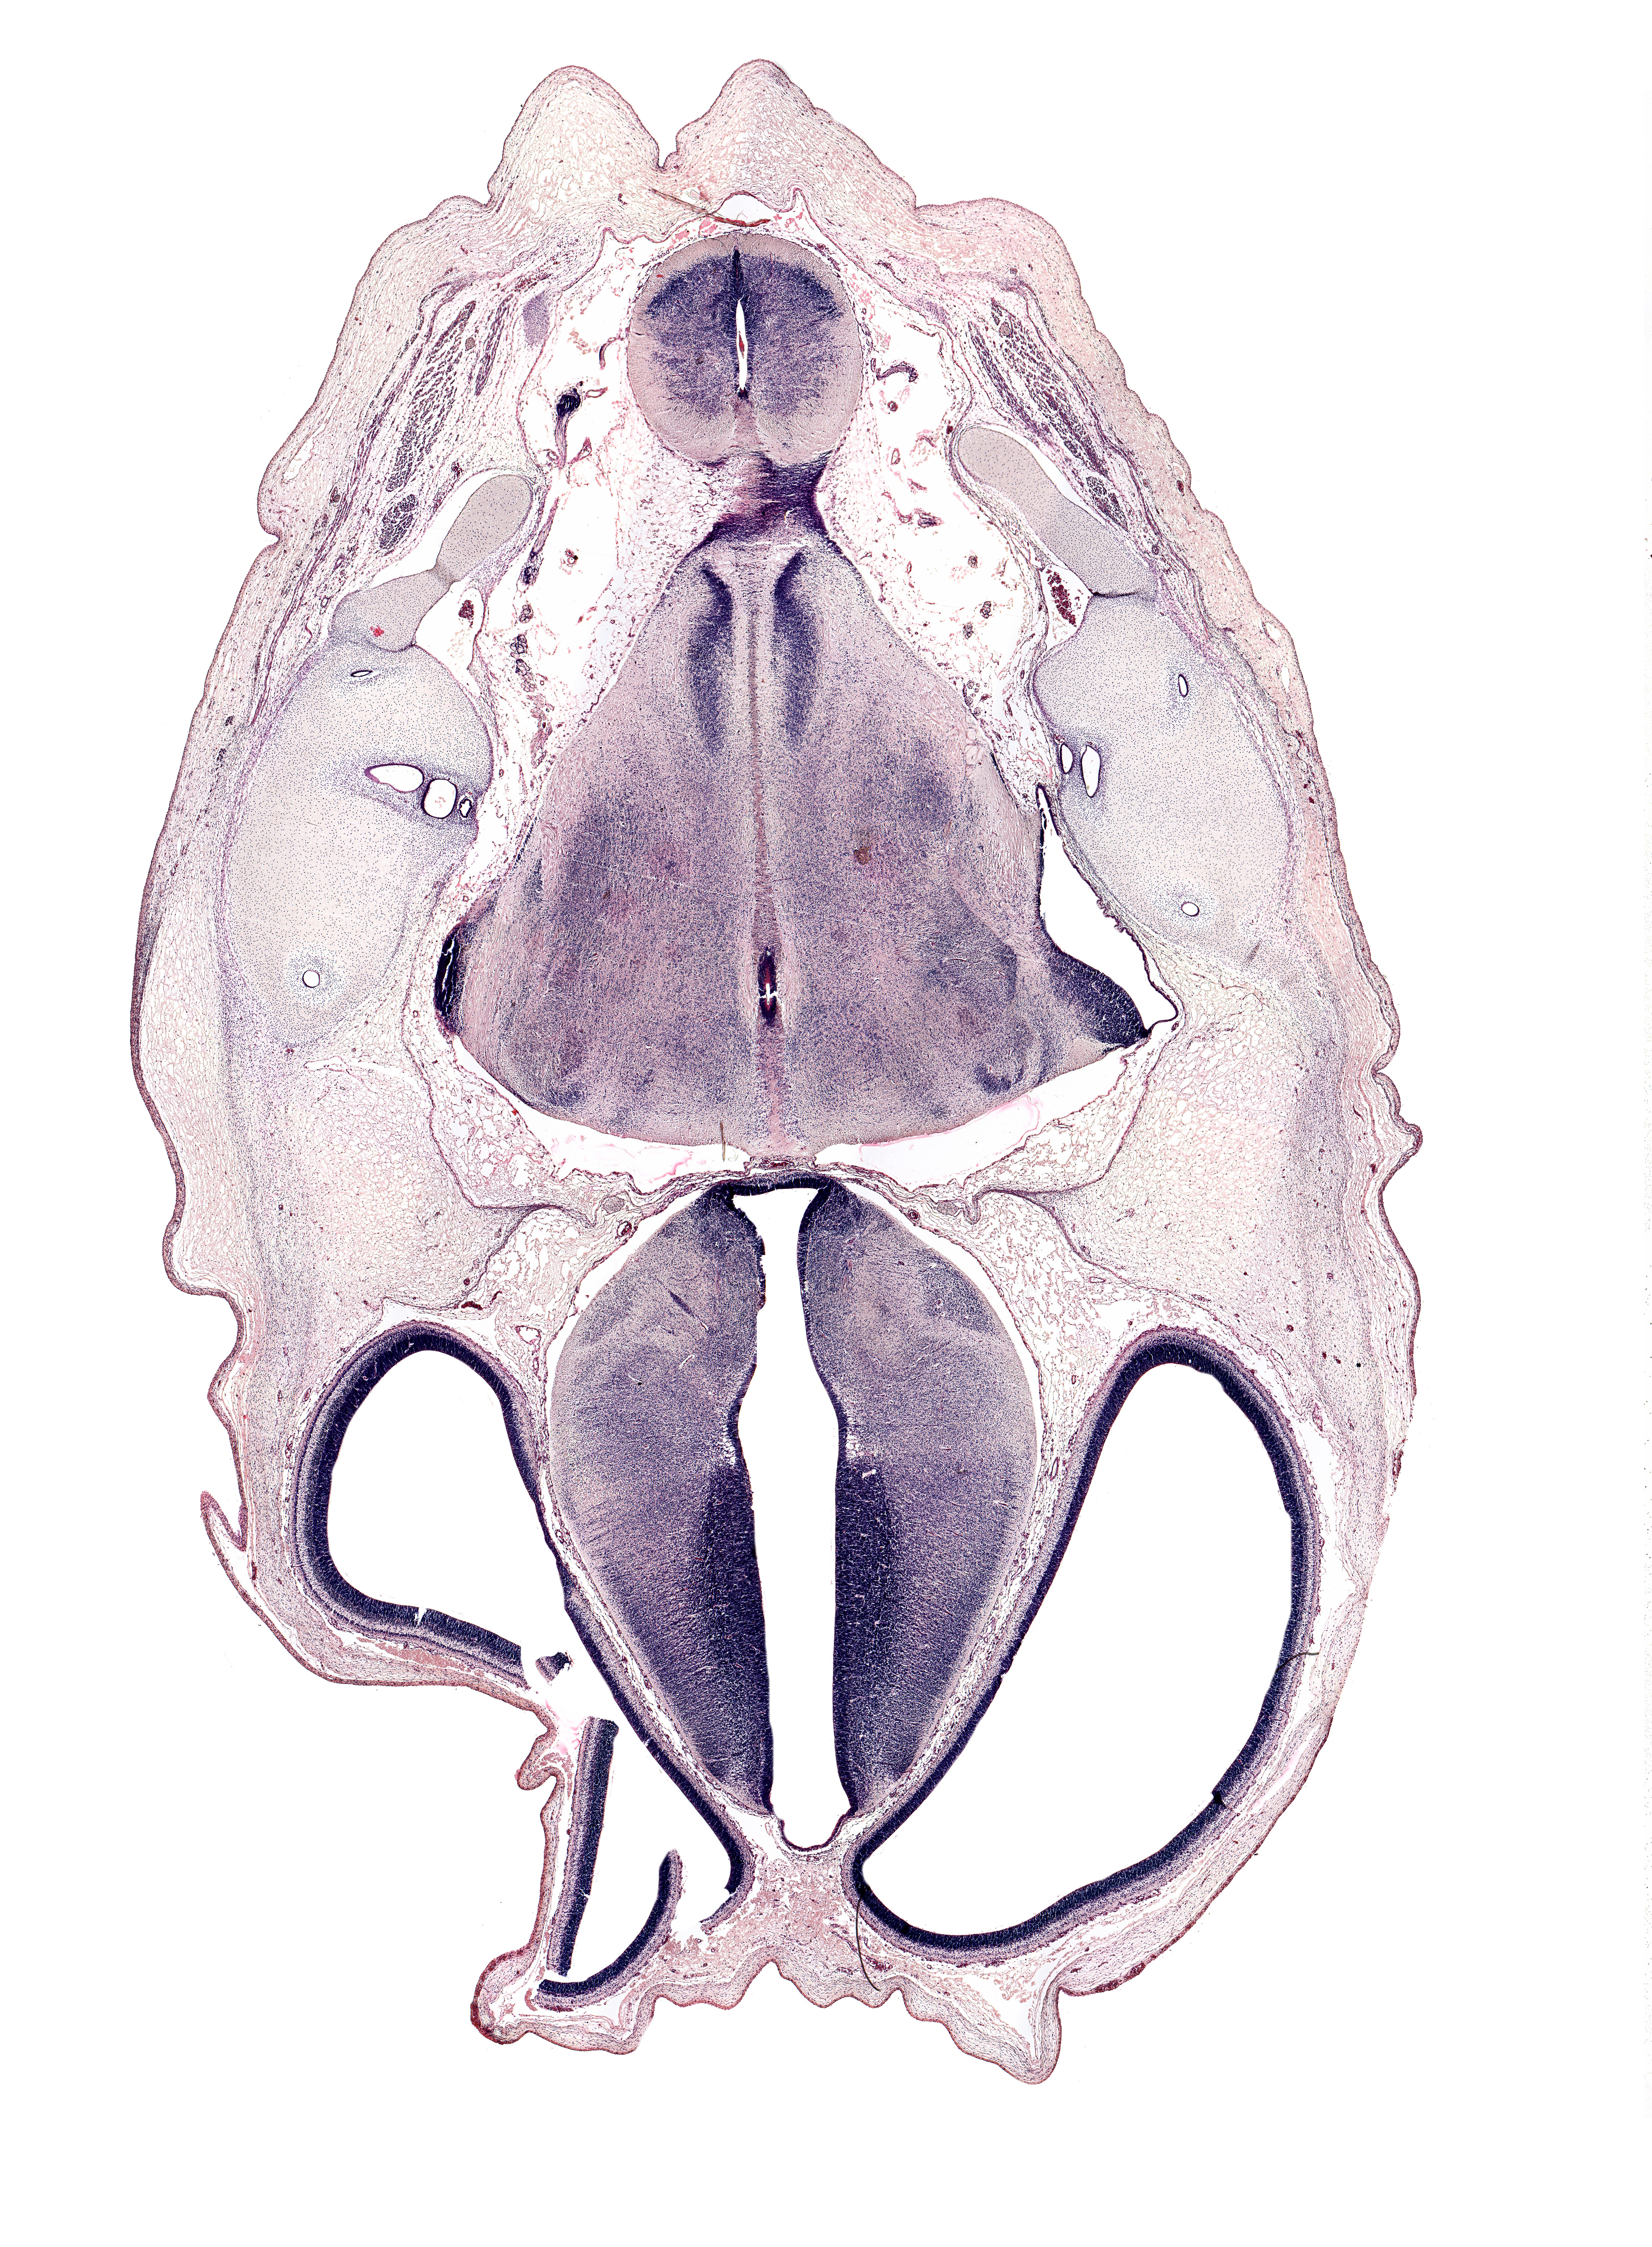

Boyd Embryo #H983 | Location: 45-1-5

Keywords: anterior semicircular duct, artifact fracture(s), artifact space(s), common crus, dorsal thalamus, dural band for tentorium cerebelli, dural limiting membrane, endolymphatic duct, exoccipital, facial nerve tract, hypothalamus, lateral ventricle, medial accessory olivary nucleus, medial longitudinal fasciculus, median sulcus in floor of rhombencoel (fourth ventricle), otic capsule cartilage, posterior dural venous plexus, posterior semicircular duct, roof plate, spinal tract of trigeminal nerve (CN V), subarachnoid space, third ventricle, ventral thalamus, zona limitans intrathalamica

Source: The Virtual Human Embryo.